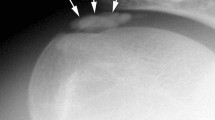

Plain radiography

Most authors regard radiographs of secondary importance to physical examination. Kager et al. [47] described a triangle seen on the lateral radiograph that is fat filled and bound by the margins of the anterior border of the AT, the posterior tibia and the superior calcaneus. Following rupture, the anterior border of the AT approaches the posterior aspect of the tibia and the triangle loses its regular configuration. In addition, the Toygar sign [48] involves measuring the angle of the posterior skin surface on the lateral radiograph, given the ruptured tendon ends displace anteriorly.